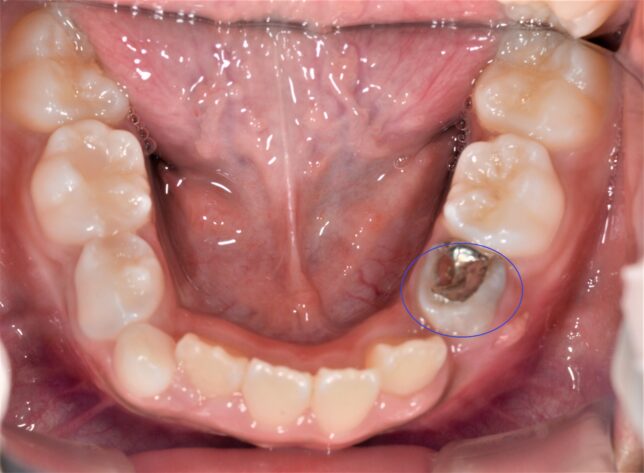

たしかに重度の歯周病があったり、被せ物が多かったり、既に失っている歯があったり、インプラントが入っているといった要素があると、矯正が難しくなる場合もあります。

実際に、その方は噛み合わせが悪く、このままだと好ましくないと診断しましたので、「した方がいいと思います。」とお答えして、連携している矯正専門医のクリニックにご紹介しました。